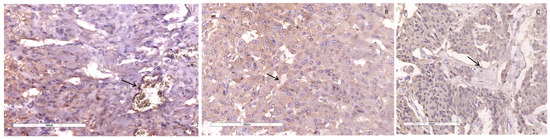

3.2. Microscopic and Immunohistochemical Findings